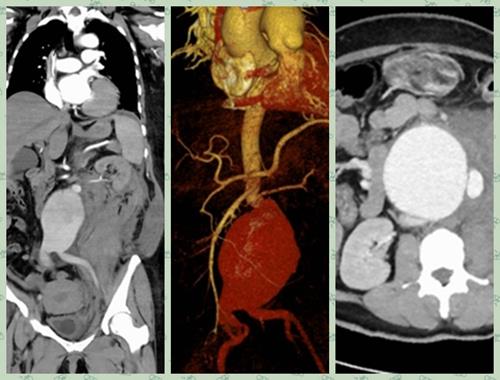

成功救治一例巨大破裂性腹主动脉瘤

普外一科医生雷跃华等人早在一旁严阵以待,立即联系CT室急诊CTA检查,结果提示患者动脉瘤随时有破裂的可能,时间就是生命,情况十分危急。从CT上来看,患者动脉瘤瘤体紧贴双肾动脉,瘤颈短且扭曲,丧失腔内介入治疗机会,雷跃华立即将情况报告给了主任杨玉辉、副主任魏健。得知情况,杨玉辉立即做出指示,患者病情危急,必须立即手术,抢救患者生命。

手术中,发现患者腹膜后出现巨大血肿,约30x15cm大小,瘤体及腹腔内大量积血。时间紧急,立即用血管阻断钳紧贴肾动脉阻断血流,切开瘤体见瘤体后壁一长约6cm破口,成功切除动脉瘤体,并用人工血管进行腹主动脉及双侧髂动脉吻合,吻合口无出血。